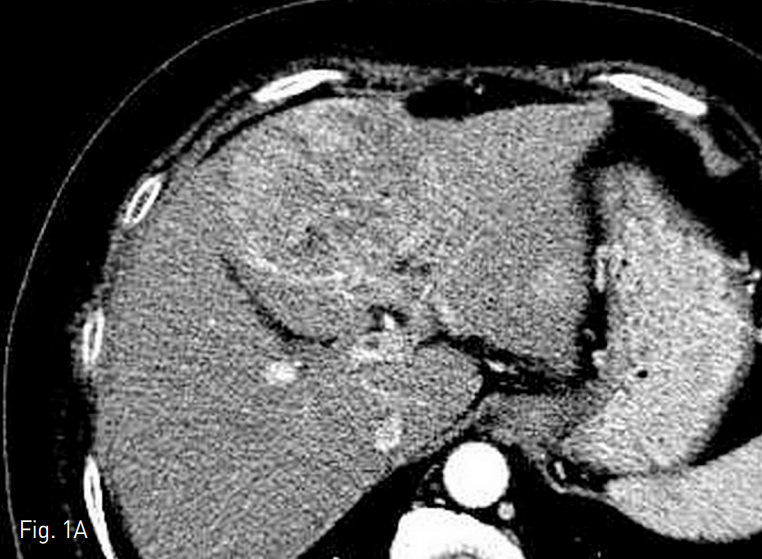

간의 4번 구역에 장경 7.5cm의 간세포암이 있었으며 (Fig. 1A), daughter nodule들이 구역 3, 4, 8번에서 각각 2cm 미만의 크기로 발견되었다. 간문맥의 umbilical portion에서 종양 혈전증이 동반되어 있었다 (Fig. 1B). 이밖에 원격 전이의 소견은 보이지 않았다.

Fig. 1. Computed tomography before transarterial radioembolization

A. There is a 7.5cm sized hepatocellular carcinoma in the liver segment 4 on arterial phase image. Three more daughter nodules are noted (not shown) in segment 3, 4, and 8.